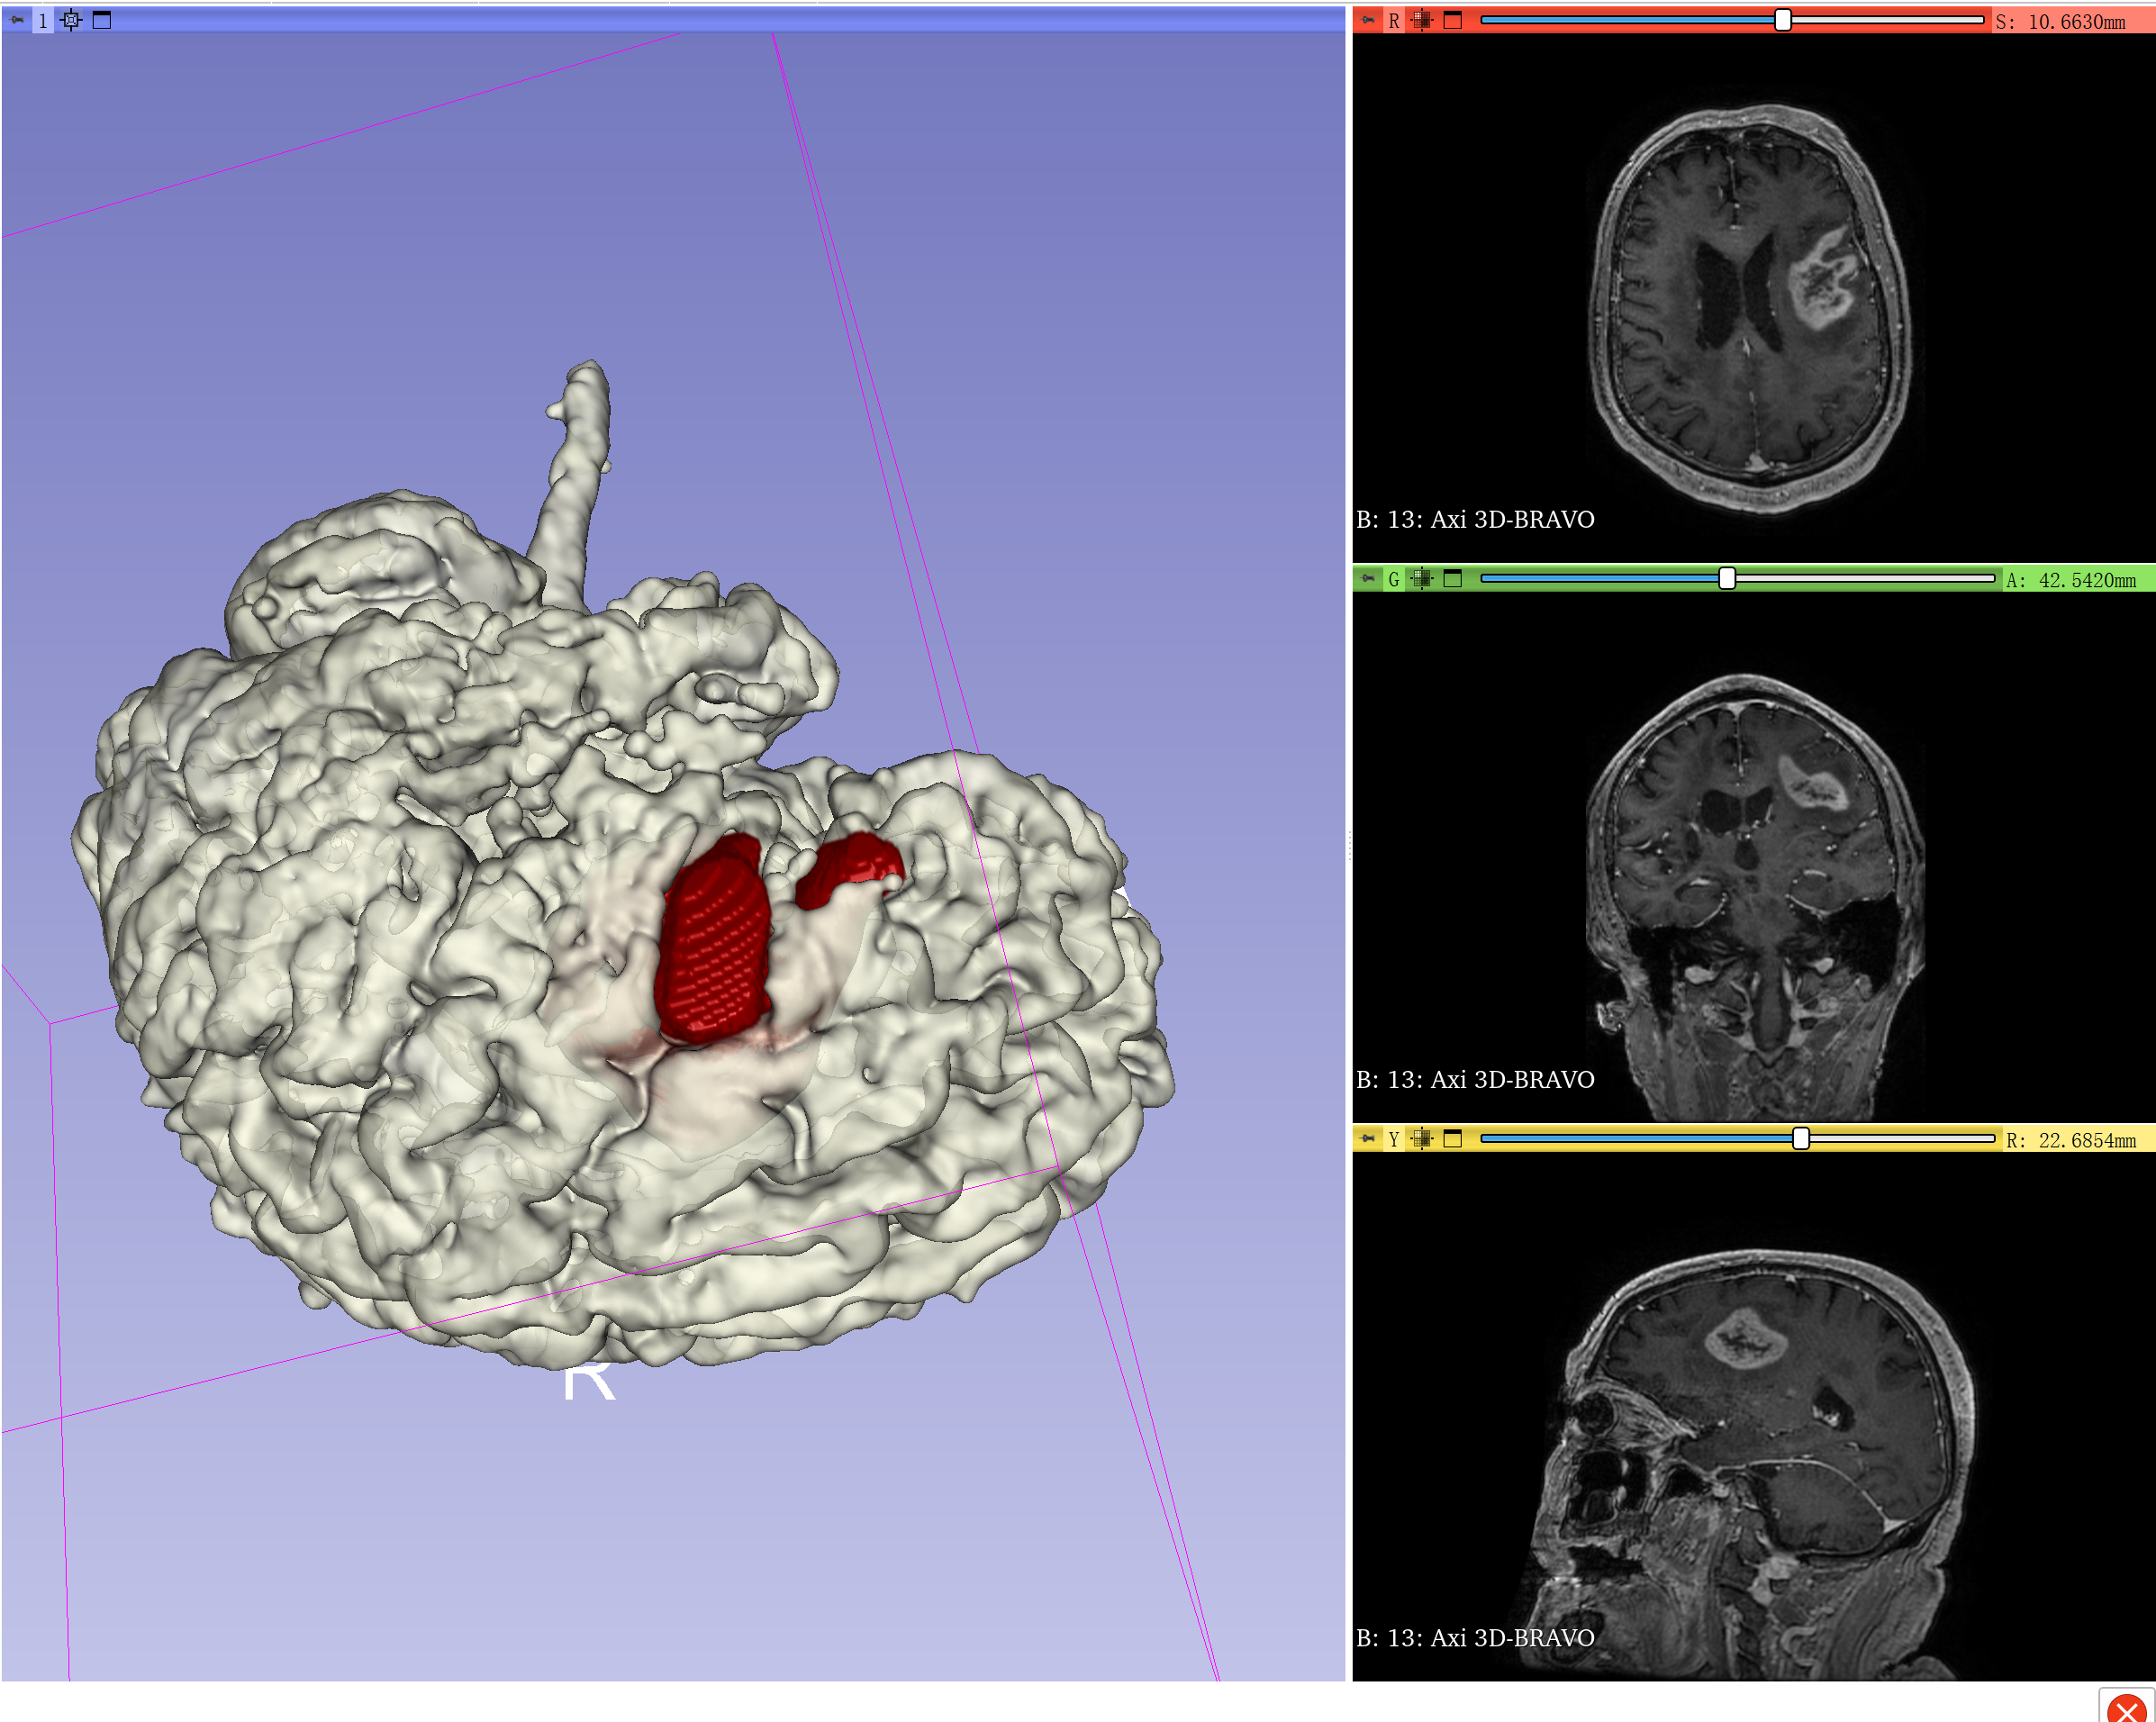

结合勾画出来的肿瘤,显示肿瘤侵犯额下回三角部、岛盖部和中央前回下部。